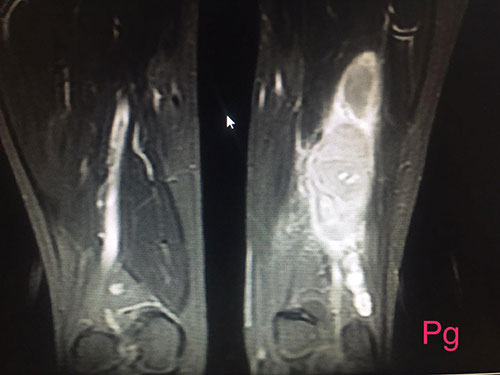

15yrs old girl with large sciatic nerve tumor wondering since 1yr in Jaipur, open biopsy was done elsewhere diagnosed as neurofibromas and she land up with infected bad biopsy scar with discharging sinus

I operated her 5days back with complete removal of tumor along with biopsy scar and track with dissecting nerve fibers from mass and now she has no neurological deficits and full range of movements of knee and foot